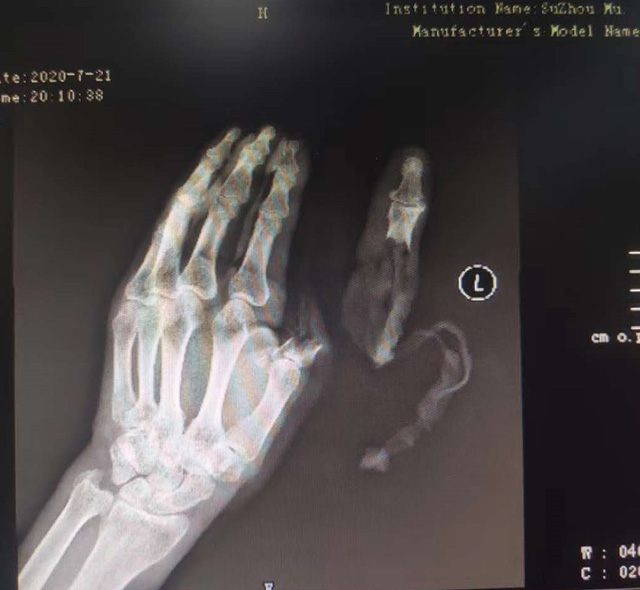

△老人送醫(yī)時的手部狀態(tài) 蘇州市立醫(yī)院供圖

現(xiàn)代快報記者了解到,7月21日下午,這名76歲的老人在家擦拭面粉機時,忘記關(guān)閉電源,結(jié)果抹布被纏進機器,順帶著將老人的手也帶進機器中。老人奮力掙脫,可為時已晚,待將手取出時,已經(jīng)血肉模糊,大拇指在脫落后還被絞入機器軋了一圈……

拇指可以影響一只手40%的功能,為此醫(yī)院立即制定了手術(shù)方案,決定為老人進行斷指再植術(shù),盡力為其保住拇指。由于該患者年紀大、血管彈性差,動脈血管分層也很嚴重,面對重重困難,醫(yī)生在顯微鏡的輔助下,小心翼翼地將血管、神經(jīng)重新吻合,并修復肌腱、皮膚。經(jīng)過5個多小時努力,最終再植成功。